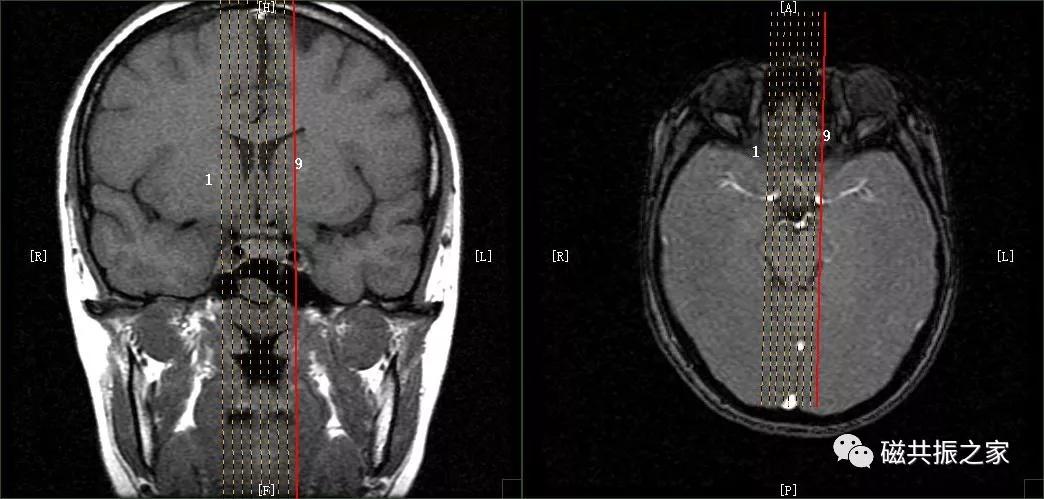

冠状位:COR T1 FSE 冠状位T1加权序列

以矢状位和横断位作为参考定位。在矢状位上定位线垂直于鞍底(或平行于垂体柄或垂直于垂体窝),在横断位上与大脑纵裂垂直,双侧对称扫描,扫描范围包括整个垂体,根据病变大小调整范围,需包括整个病变范围。

冠状位是观察垂体柄形态和测量垂体高度最理想的方位。

FOV不宜过大,14~18cm。

相位编码方向为左右。

添加上下、前后饱和带可减轻脑脊液,血管搏动伪影。

如在矢状位图像上垂体柄倾斜的角度超过45°,建议采用定位线垂直于鞍底或垂直于垂体窝的方式定位扫描。

最理想的冠状位图像:同一层面视交叉、垂体柄和垂体均能清晰显示,共同组成“工”字结构。